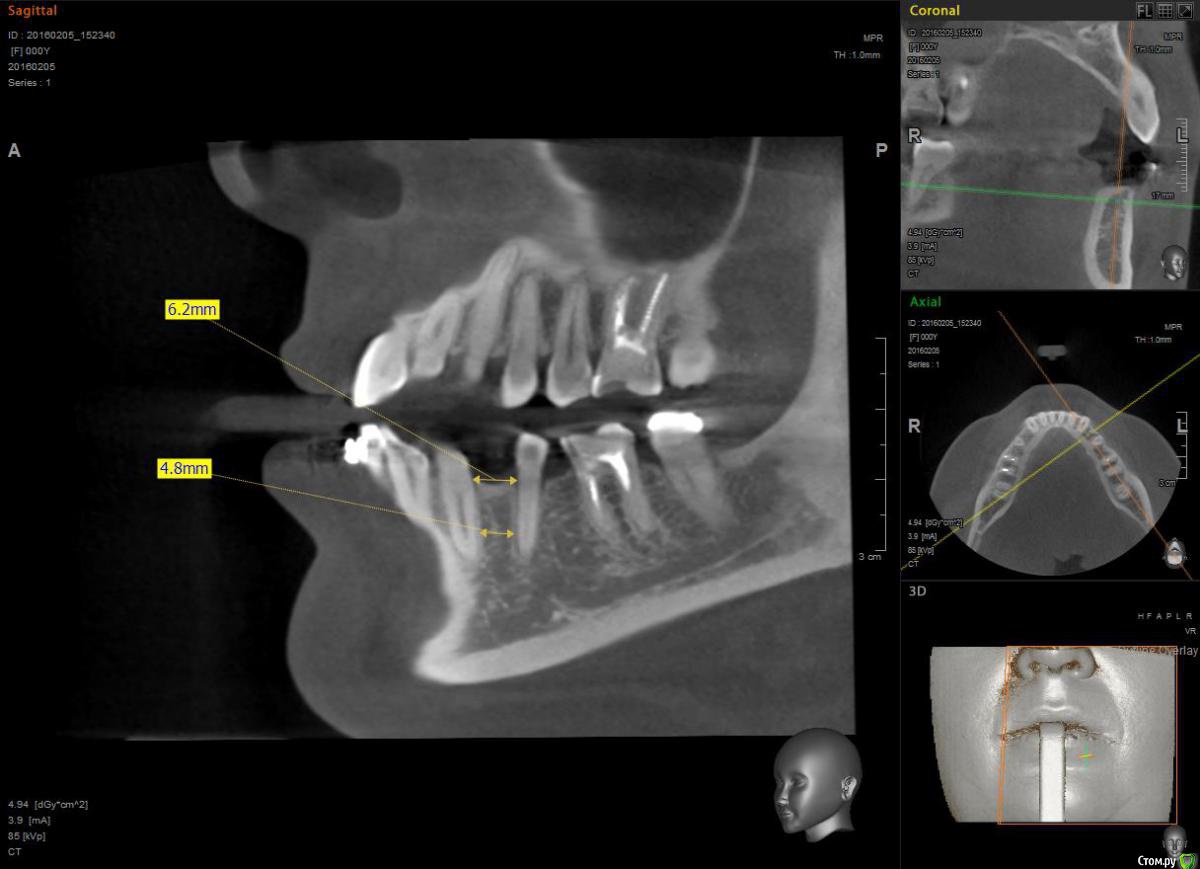

Janila Опубликовано 17 февраля, 2016 Поделиться Опубликовано 17 февраля, 2016 Прошу совет. Планирую установку имплантов на место не выросших нижних 4к. Стоят брейкеты. Имплантолог увидев снимки сказал места еще мало, и нужно сместить корни пятерок в параллель с шестерками. Иначе импланты погубят соседние зубы.Ортодонт сказал, что сдвинуть корни не возможно. Места мало, только под 3мм системы. Что делать, кому верить.Вариант с установкой мостов не рассматриваю. Ссылка на комментарий

Janila Опубликовано 2 августа, 2017 Автор Поделиться Опубликовано 2 августа, 2017 (изменено) Отчитаюсь по итогам своих мытарств. Была еще у 2х ортодонтов, один сказал, что можно, но с данной системой не работает, второй, видимо не хотел связываться, и сказал, что лечение обойдется в 30 тыс. (с уже установленной системой).Имплантацию сделали в августе 2016 года. Сейчас считаю, что поспешно, под давлением ортодонта. Были у меня нарекания к положению нижних 1-2-3х и 5х зубов, но он уверил, что все доведем до ума после имплантации. Ладно, импланты прижились, дело шло к установке коронок, но передние зубы все не вставали, а 5ки и 6ки не могли поделить место. То 6ки заваливались во внутрь к языку, то 5ки выпадали наружу. Так длилось 4 месяца и 3и активаций. Топтание надоело, мысли о некомпетентности ортодонта вновь стали посещать. И в предновогодние дни попала по рекомендации к детскому ортодонту, заведующей отделением в детской поликлинике. Первое, что никто не замечал, это были мои переростки - 8ки верхние, которые блокировали нижний ряд! После их удаления и свободной фиксации зубов на дуге (каждый зуб отдельно, а не цепочкой), все зубки встали по местам. Благодаря ее опыту, было все доведено до ума за 3 месяца и 2 активации, но конечно из-за поспешной имплантации, ортопеду пришлось коронки делать со смещенным центром. Стоят уже месяц и меня радуют. Так длинно не для специалистов, а для пациентов. Ищите и обрящите. Ортодонт должен быть с большим стажем если у вас сложный случай! На снимке после имплантации как раз видно, что 5ки "выпали" наружу, после их возвращения в зубной ряд, они стали прилегать в плотную к формирователям десны, при этом идеально совпали в позиции с верхним рядом. PS. Из предыстории - в принципе у меня не уродилось нижних 4ок и 8ок, а после беременности и рождения ребенка нижние передние зубы начали разъезжаться веером, хотелось остановить эти изменения из-за чего было начато это приключение. Изменено 2 августа, 2017 пользователем Janila Ссылка на комментарий